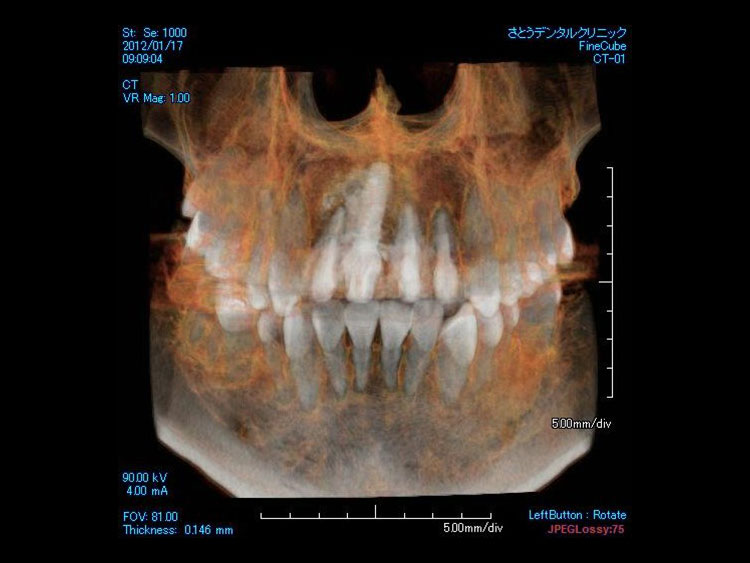

1.診査・診断

レントゲンなどによって十分な診断の後、インプラント治療に関する説明を受けます。インプラント治療は専門のトレーニングを受けた歯科医師のみが行います。

レントゲンなどによって十分な診断の後、インプラント治療に関する説明を受けます。

インプラント治療は専門のトレーニングを受けた歯科医師のみが行います。

2.インプラントを埋め込む

CT事前にシュミレーション

シュミレーション通りにインプラント埋入

局部麻酔のもと、顎の骨にチタン製のインプラントを挿入します。 このインプラントが 新しい歯の土台となります。